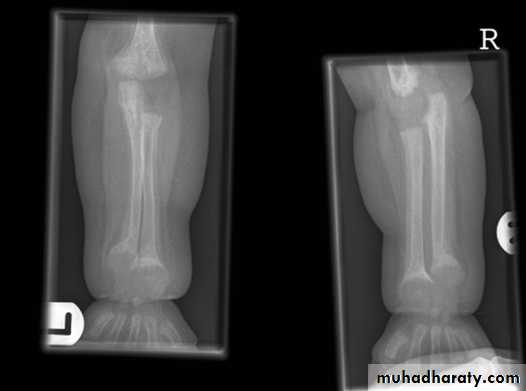

Osteomylitis :Osteomyelitis is most often caused by staphylococcus aureus & usually affects infants & children.

The initial radiographs are normal as bone changes are not visible until 10 -14 days after the onset of the infection.

the earliest sings on plain radiographs are soft tissue swelling , and bone destruction in the metaphysis with a periosteal reaction that eventually may become very extensive and surround the bone to form an involucrumpart of the original bone may die and form a separate dense fragment known as a sequestrum